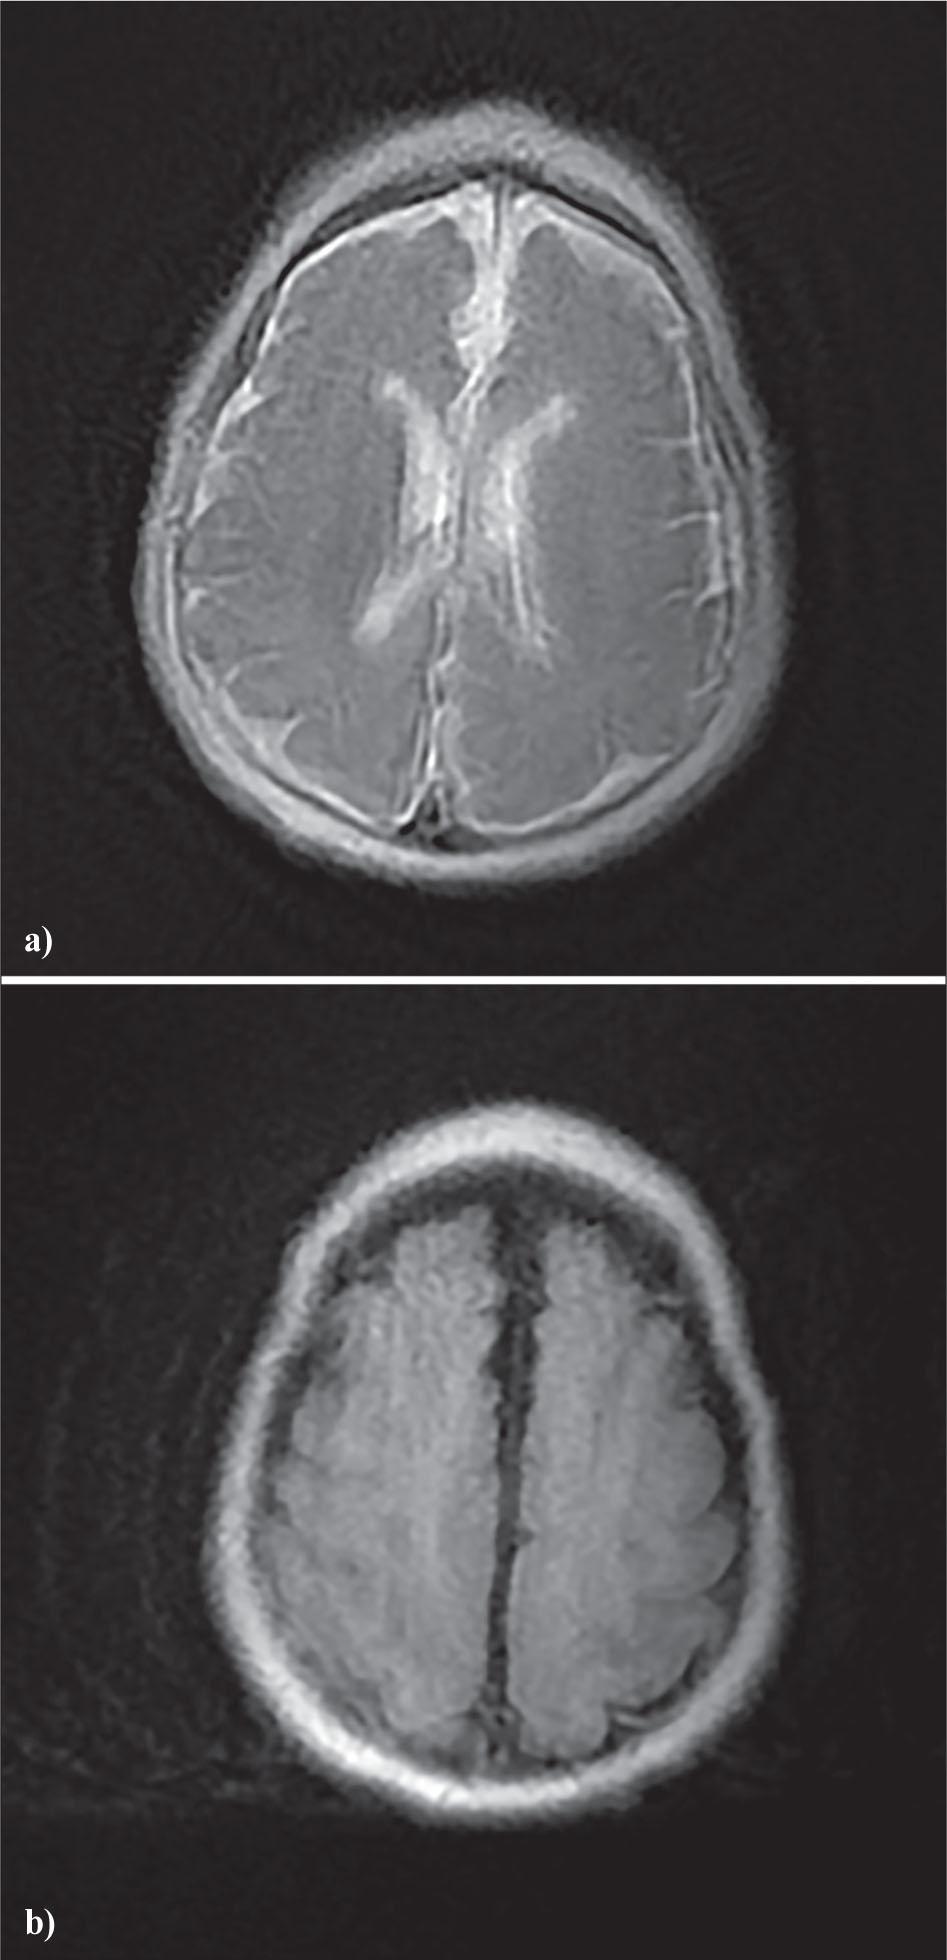

Brain MRI revealed a diffuse simplified gyral pattern (lissencephaly type 1), predominantly frontal and occipital bilaterally, associated with partial agenesis of the corpus callosum and moderate ventriculomegaly (Figure 2). At three months of age, the patient developed insulin-requiring permanent neonatal diabetes with elevated blood glucose level between 5.5 and 6.1 g/L and HbA1c at 12 % measured during his hospitalization. The insulin therapy was initiated. Management was complicated by frequent hypoglycemic episodes, requiring adjustment of insulin doses and nutritional support.

Brain MRI of the patient

(a) Axial T2-image showing partial agenesis of the corpus callosum with moderate ventriculomegaly.

(b) Axial FLAIR image showing a simplified gyral pattern consistent with lissencephaly.